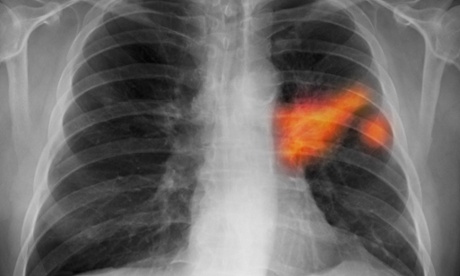

Chest x-ray of a smoker showing lung cancer in the left lung.

Chest x-ray of a smoker showing cancer in the left lung. AstraZeneca’s cancer portfolio formed a key plank of its defence against a £69bn takeover attempt by Pfizer last year. Photograph: Kallista Images/Visuals Unlimi